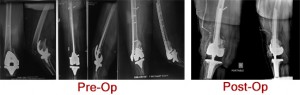

Kamala Devi 57 Years old lady presenting with pain and inability to bear weight on right lower limb. Patient developed intraoperative supracondylar fracture of the femur during TKR in Feb 2011 . 4 days later Open Reduction Internal Fixation with Retrograde Intramedullary Nailing was done. Implant failed and revision surgery ... Read more..